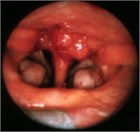

1. 上咽頭癌は日本では8割ほどがEpstein-Barr ウイルス(EBV)陽性の非角化型、残りはEBV陰性の角化型である。